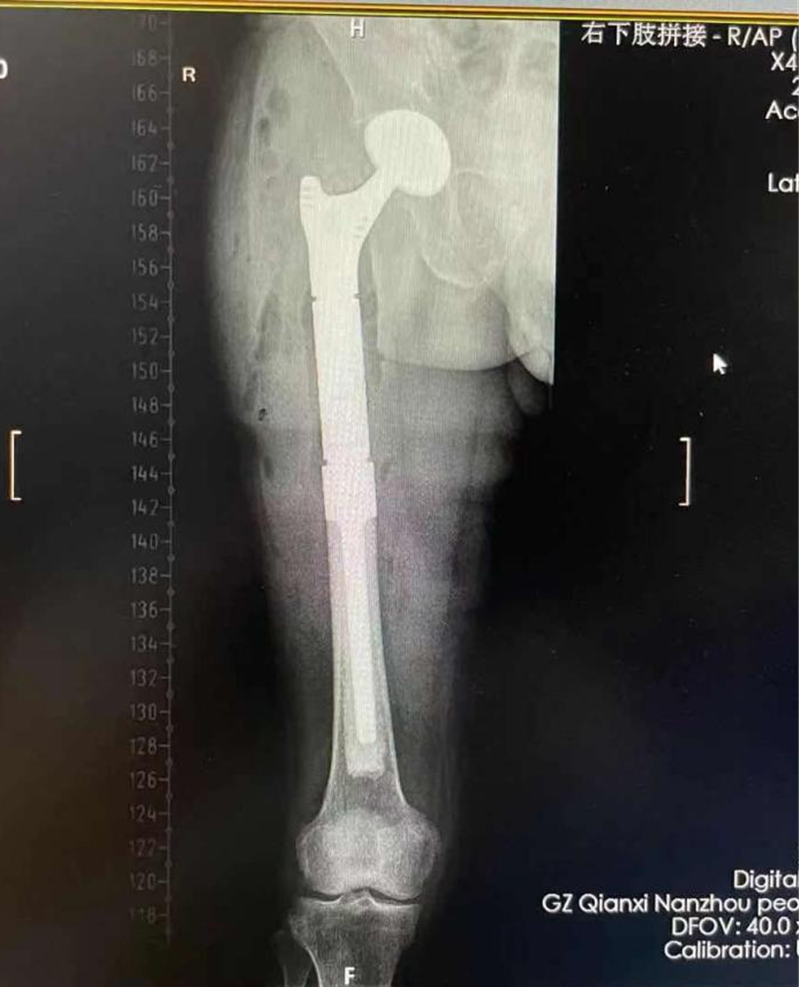

患者陈某,68岁,右下肢剧痛不能行走,经检查确诊为右股骨上段骨肉瘤病理性骨折。考虑到患者“髋关节下病变没有支撑”,关节外科为其施行了“股骨上段骨肉瘤切除,髋关节置换重建”手术。术后经过医疗团队的精心治疗及护理,患者恢复较好,很快便能下床行走。

术后肿瘤切除,股骨和髋关节重建